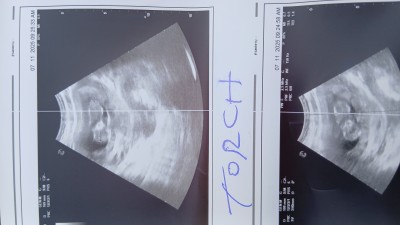

Ultrason Sonucu ile Cinsiyet Tahmin Edilir mi?

Ultrason sonucu cinsiyet tahmini yapar mısınız

Gebelik haftası

12